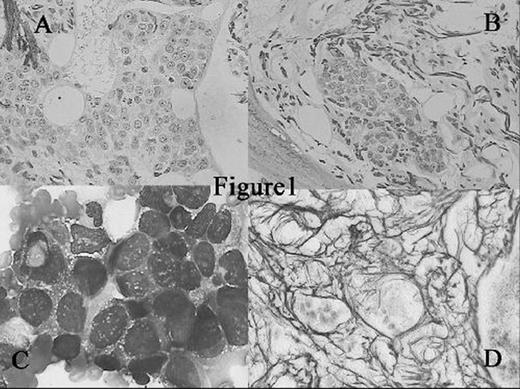

Overall 101 of the 10112 BM samples showed nonhematological tumor metastases, accounting for 1.0% of all analyzed specimens, which was higher than data reported on the basis of paraffin embedded samples. Of 74 aspiration smears obtained concurrently with the 101 biopsy sections, 55 were also positive for metastatic carcinoma. That is, the detection rate of metastatic tumors based on the aspiration smears was 74.3% relative to the rate observed on biopsy sections. All 101 sections with metastatic tumors showed various degrees of myelofibrosis (including 67cases with severe myelofibrosis [+++]) which was thought to be partly responsible for false negative results on aspiration samples. Primary tumors were documented ante-mortem in 50 of the 101 BM biopsy-positive patients (49.5%). The most frequent primary sites were lung, gastroinyestinal tract, and breast, in good agreement with data in the literature. In conclusion, nonhematological tumor metastases in unselected bone marrow are not exceptional findings. Plastic embedded BM biopsy examination is helpful in detecting unknown metastatic nonhematological malignancies and apparently more sensitive than paraffin embedded BM biopsies.